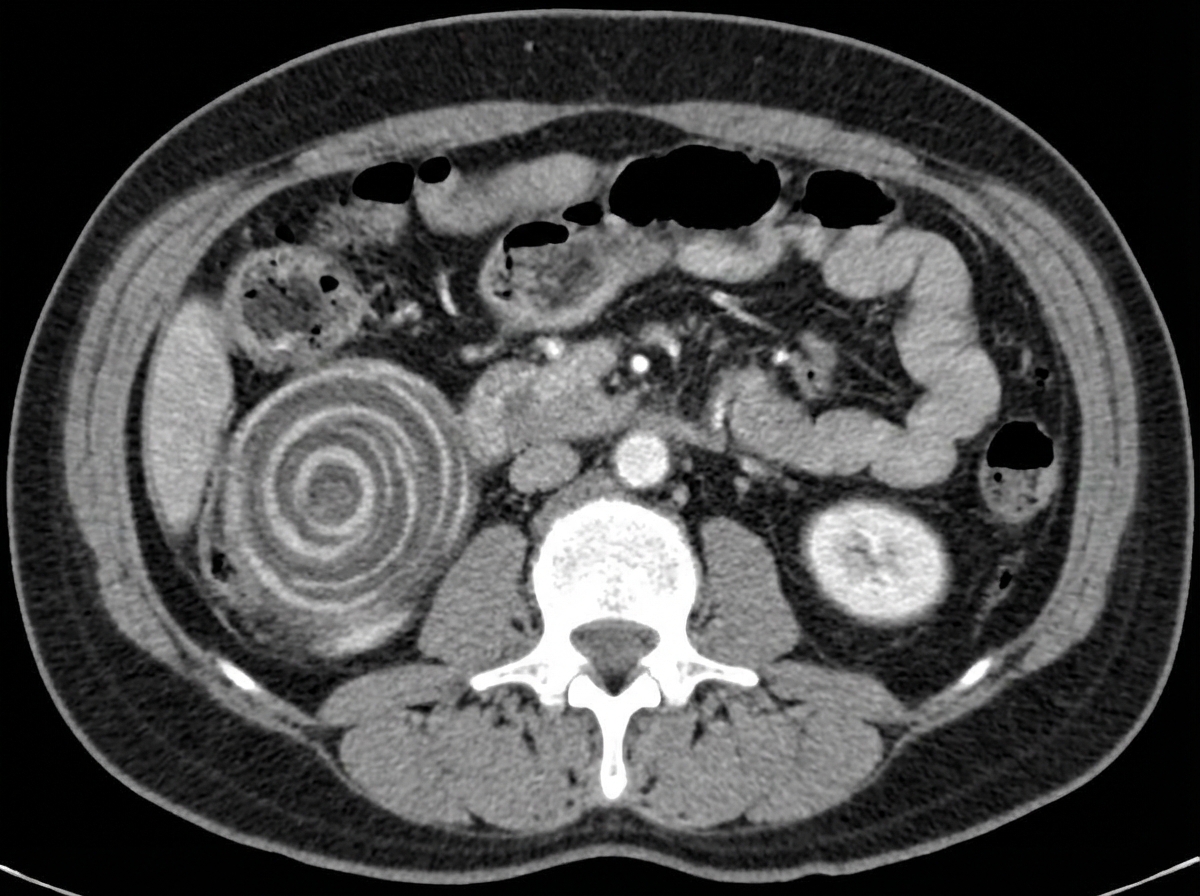

Explanation: ***Resection with anastomosis*** - **Adult intussusception** has a high association with **malignant lead points** (>90%), making surgical resection mandatory to address the underlying pathology. - **Gangrenous bowel** from prolonged obstruction requires immediate resection to prevent **perforation** and **sepsis**. *Sigmoidoscopy* - Used for **sigmoid volvulus decompression** but not effective for **intussusception** where the bowel is telescoped and obstructed. - Cannot address the underlying **malignant lead point** commonly present in adult intussusception cases. *Conservative management* - Inappropriate for **surgical GI emergencies** like intussusception where bowel viability is compromised. - Risk of **bowel perforation**, **necrosis**, and **septic shock** makes conservative approach dangerous. *Hydrostatic enema* - Effective only in **pediatric intussusception** where lead points are rare and reduction is often successful. - **Contraindicated in adults** due to high risk of **malignant lead points** and potential for **bowel perforation** during reduction attempts.